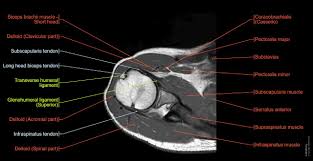

5. Imaging of Shoulder by Dr. Zainab Vora

A must-watch lecture for residents looking to master shoulder MRI. Dr. Zainab Vora simplifies complex anatomy and provides a systematic approach to identifying common shoulder pathologies.

Key Highlights:

• Systemic MRI protocols for axial, coronal, and sagittal sequences.

• Diagnosis of rotator cuff and labral injuries using advanced techniques like ABER views.

• Clear differentiation of T1, T2, and PD sequences for better accuracy.